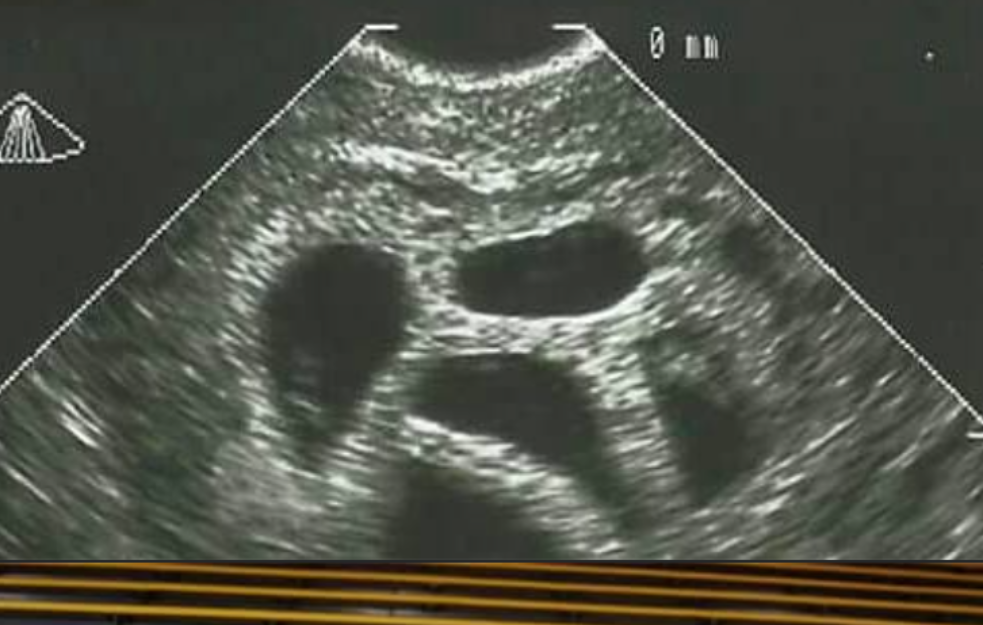

U svetu u kojem se svaka odluka o životu pretvara u debatu, priča Amerikanke Suzan Tompson vraća fokus na ono što je suštinsko - na veru, ljubav i hrabrost da se veruje u nemoguće. Imala je samo 28 godina kada je saznala da nosi petorke.

Lekari su bili direktni; savetovali su joj selektivni abortus, objašnjavajući da je trudnoća rizična i da "nije realno" da sva deca prežive.

- Moj ginekolog mi je više puta predlagao da razmislim o smanjenju broja embriona - da abortiram troje, možda dvoje dece. Ali moj muž i ja nismo o tome ni pomislili. Znali smo da, ako ih je Bog poslao, On će se i pobrinuti za njih, prisetila se Suzan.